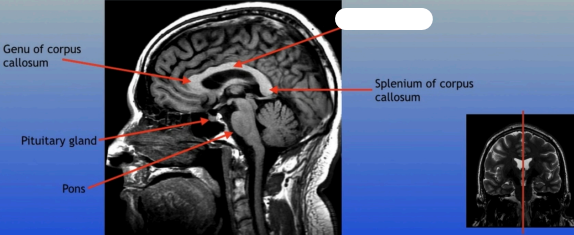

Genu of Corpus Callosum

Pituitary Gland

A small pea-sized gland located at the base of the brain, often referred to as the "master gland" because it regulates many bodily functions through hormone secretion.

Pons

A round structure located above the medulla oblongata and below the midbrain, it acts as a relay station for signals between the cerebellum and cerebrum, and plays a role in regulating sleep and arousal.